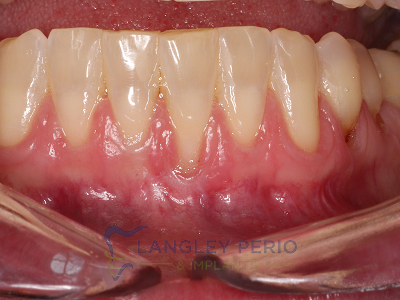

Case 2

Connective tissue grafting was done to cover exposed root surfaces to help to prevent root cavities from developing and reduce temperature sensitivity.